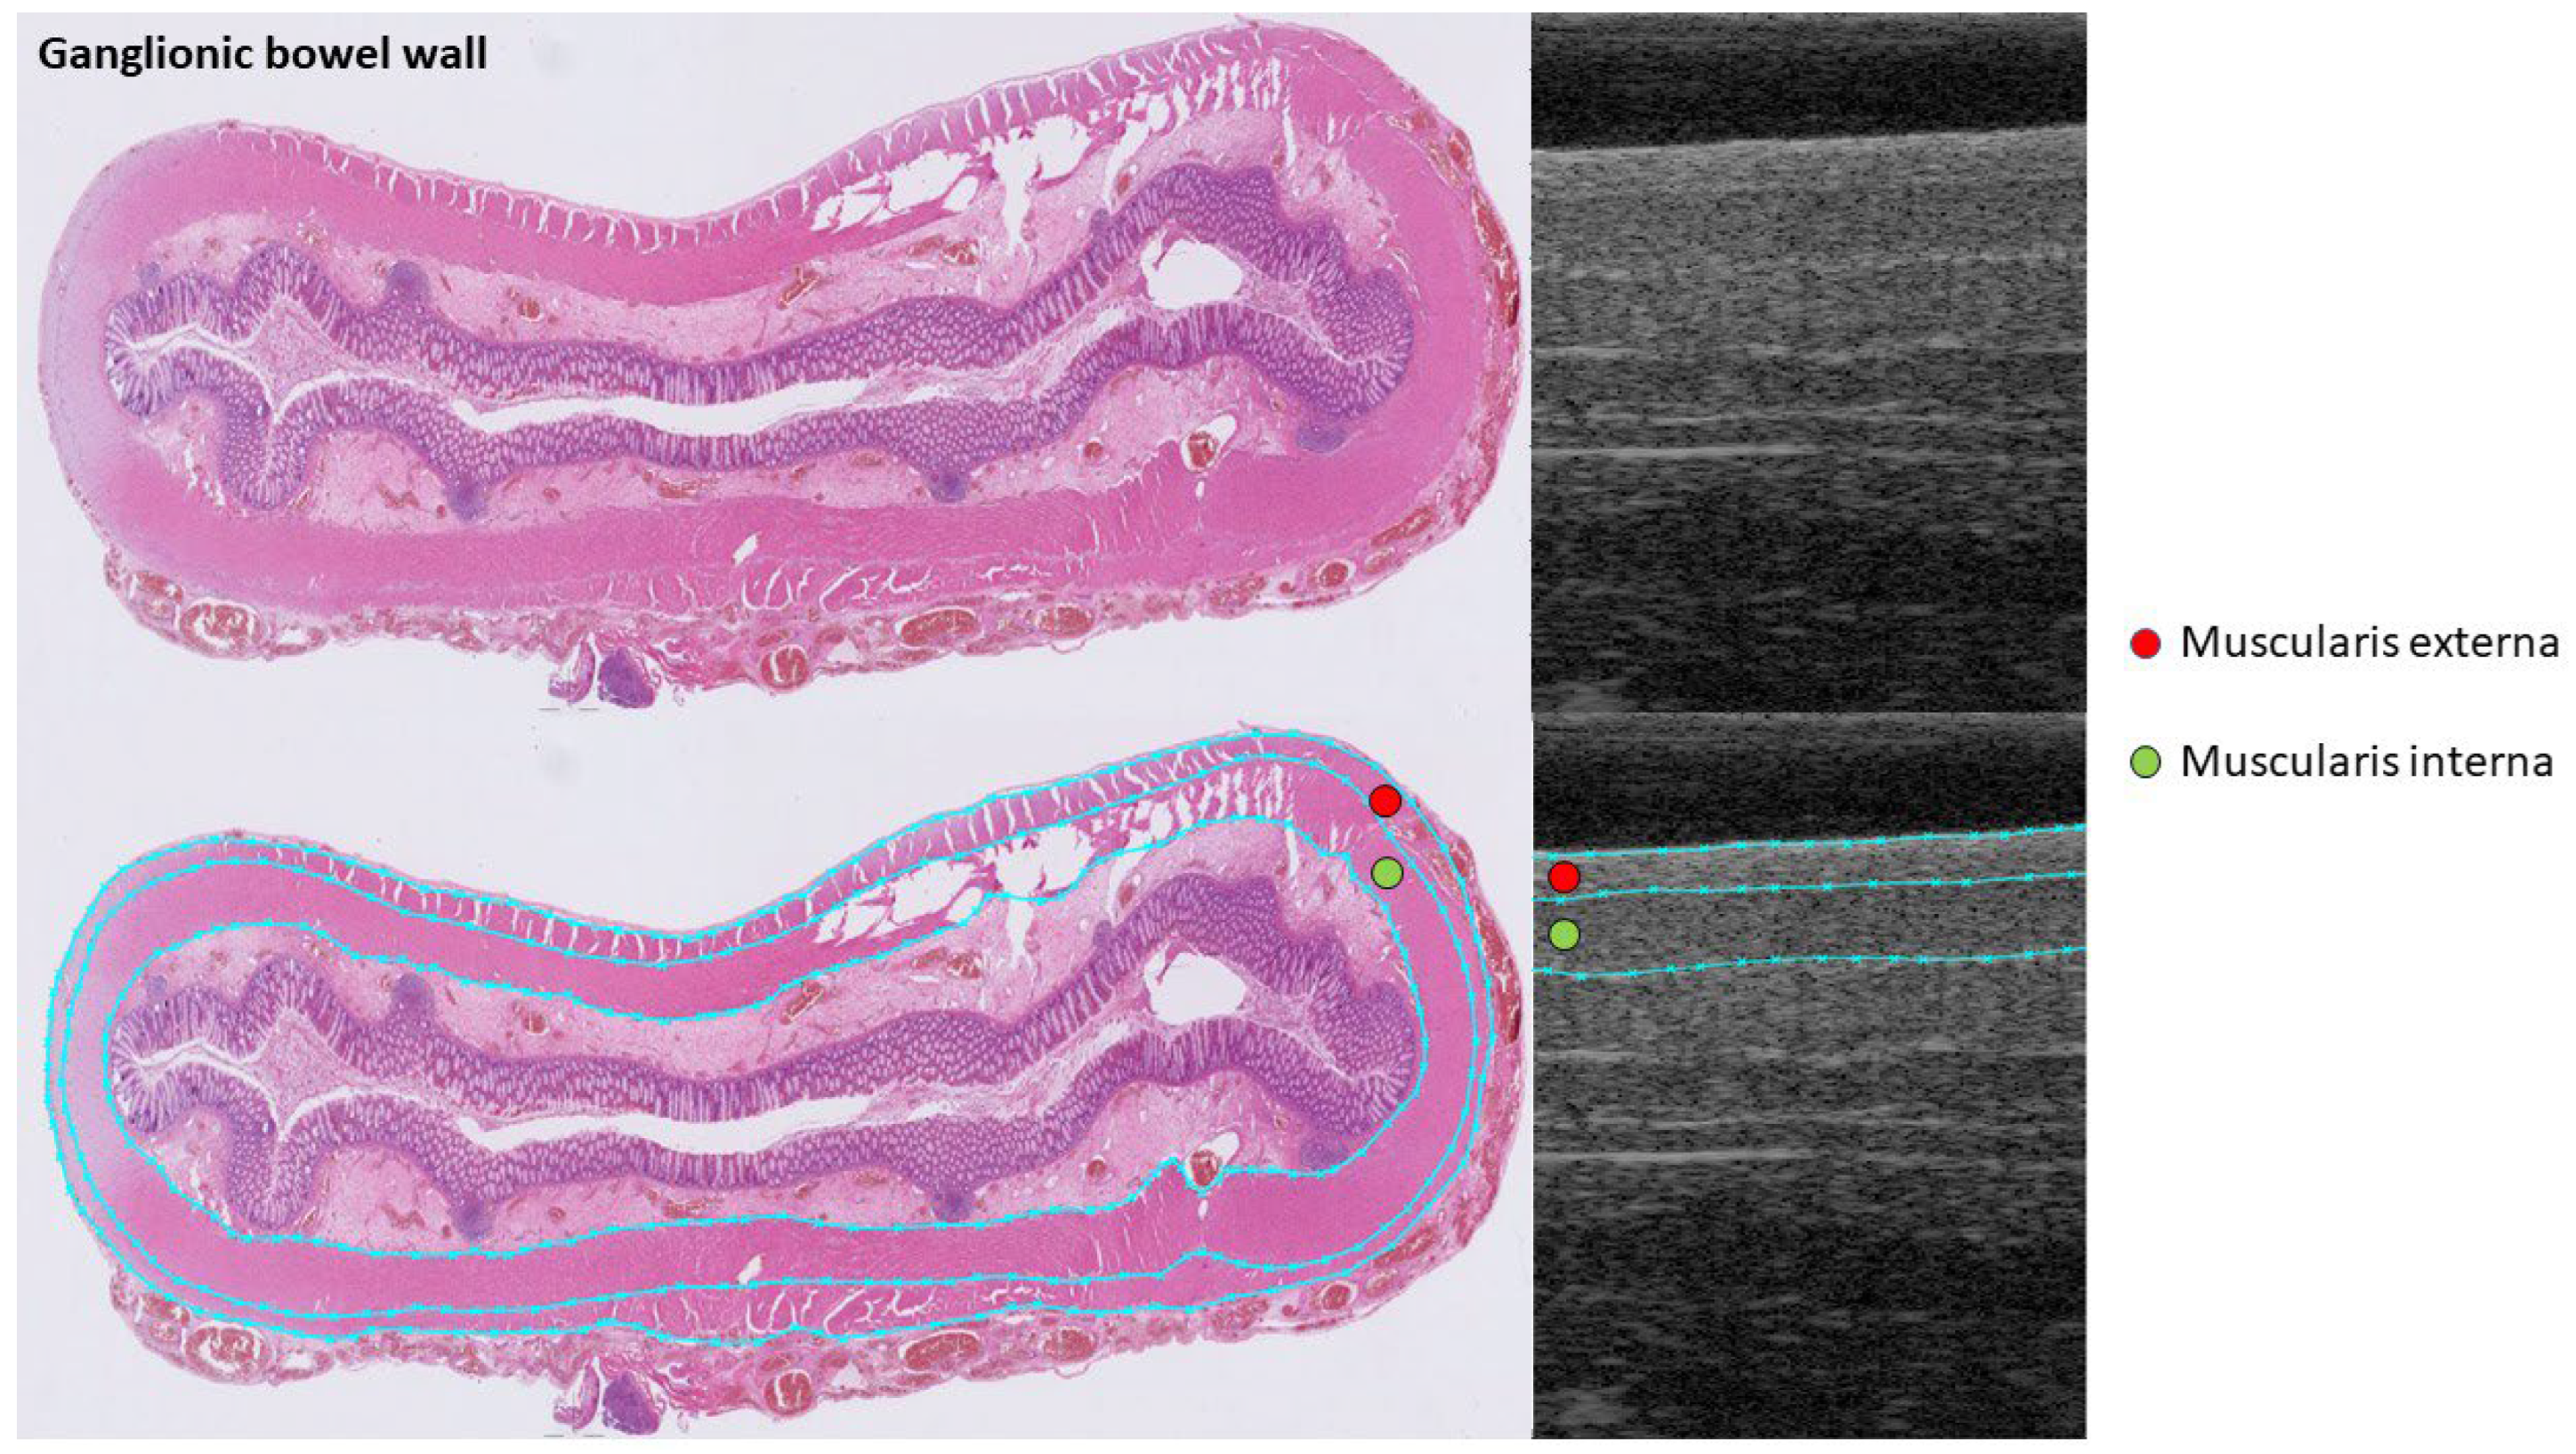

3.4. Agreements